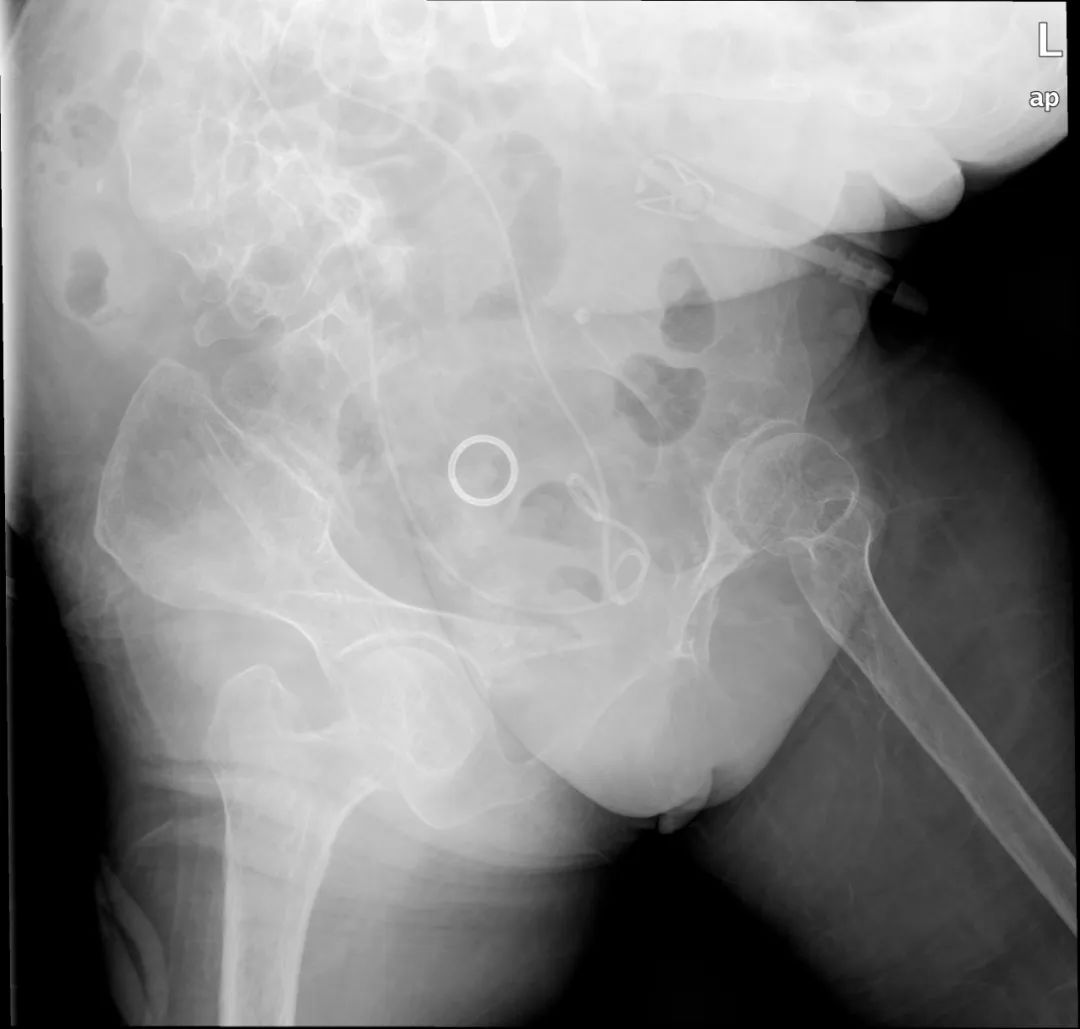

▲治疗后复查KUB双侧尿路未见明显结石影

虽然危急情况解除,但是患者的结石病情还需继续治疗,否则拔出造瘘管后患者病情仍会复发甚至加重,毕学成主任组织科室医护多次讨论并多次携带彩超机到床旁模拟手术体位,将手术治疗方案反复斟酌、完善,选择最适合患者的手术方式,在感染控制后先后安排右侧经皮肾镜碎石取石术、经尿道输尿管软镜下左肾结石碎石术等治疗,将患者体内结石取净。经过精心的治疗,患者终于取得满意的疗效出院。